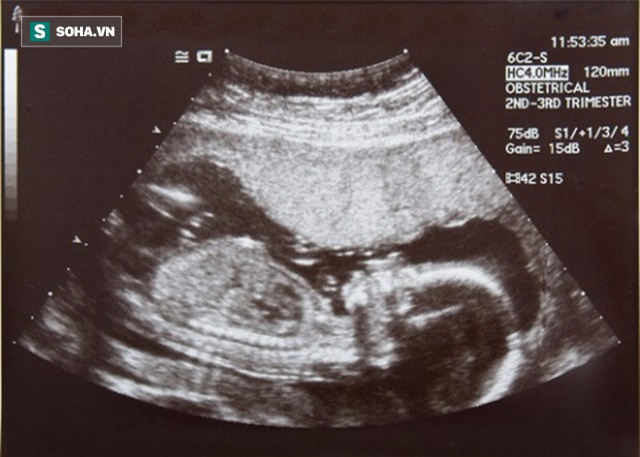

Ảnh minh họa.

Theo nội dung đơn tố cáo của vợ chồng anh Phan, tháng 7/2012, chị Cao đến bệnh viện nói trên đăng ký bảo hiểm sinh sản và làm thủ tục thăm khám trong suốt thai kỳ. Trong quãng thời gian mang thai, chị làm siêu âm tại đây 6 lần và lần nào cũng cho kết quả bình thường.

Kết quả siêu âm được các bác sĩ thông báo bình thường nhưng trên thực tế, thai nhi bị dị tật trên tay trái. Cả 6 lần thăm khám, bác sĩ đều không thông báo với chị Cao. Ảnh minh họa.